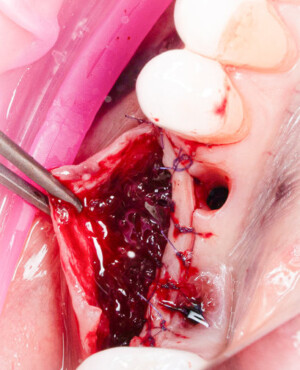

Procesul de refacere osoasă este complex, însă, simplificat, se bazează pe faptul că osul adăugat se integrează treptat, fiind înlocuit parțial cu os natural, oferind astfel suportul necesar implantului.

Un element esențial în procedura de aditie osoasă este utilizarea membranelor biologice, care izolează materialul osos de țesuturile moi (gingie) pe durata procesului de vindecare. Cele mai recomandate sunt membranele resorbabile din colagen sau pericard.